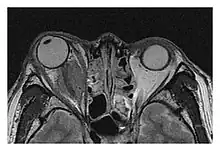

| Mass lesion around the right optic disc in a 44-year-old man with IgG4-related ophthalmic disease and a serum IgG4 of 599 mg/dL.[1] (T2-weighted MRI) | |

The extent of inflammation that can occur in IgG4-ROD is well demonstrated on magnetic resonance imaging (MRI).